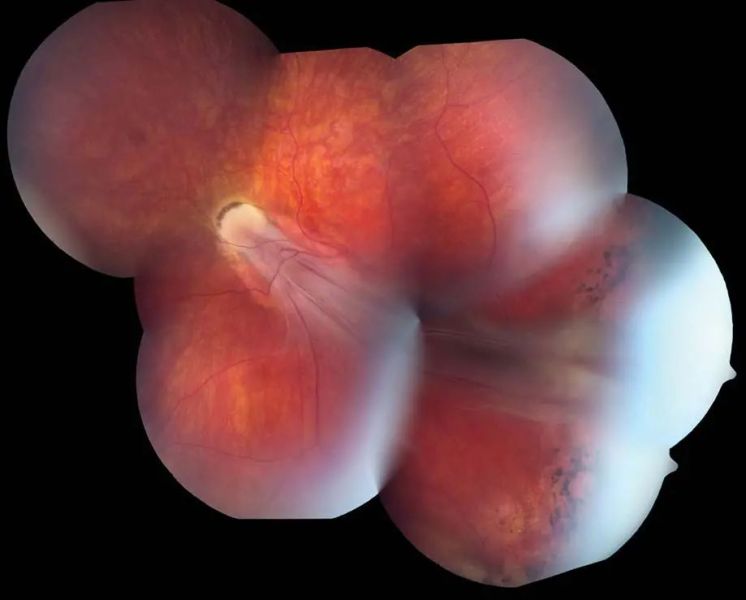

Retinopathy of prematurity is an eye condition that primarily affects premature babies, born before 31 weeks of gestation or with a birth weight below 2.75 pounds (1.25 kg). ROP occurs when abnormal blood vessels develop in the retina, the light-sensitive tissue at the back of the eye, potentially leading to scarring and detachment, which can cause vision impairment or blindness if left untreated.